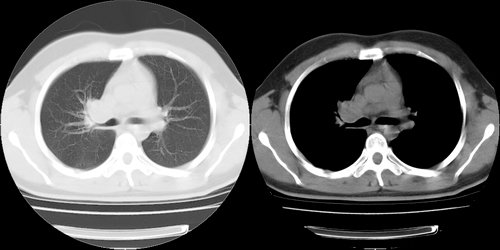

患者 男性 25岁,体检觉得右肺门感觉增大,请会诊,有没有异常?(我科诊断:未见异常)

右肺门增大,囊状影与肺动脉分支有关,上叶支气管受压移位。

考虑发生于右肺动脉分支的肺动脉瘤。

鉴别:肺结节病,多侵犯两侧肺门及纵隔淋巴结。

右主支气管及右中叶支气管受压,腔静脉后淋巴结肿大,不知肿块是血管还是淋巴s

应该是主肺动脉,随然略扩张,但够不上动脉瘤。此病理正常

右肺门前方[右侧上叶支气管尖后段分支水平]结节灶,隆突前似有淋巴结显示。结核或肿瘤。建议增强检查

建议增强,右肺上叶前段支气管受压变细,腔静脉后方见肿大淋巴结.考虑结节病或肺门占位.